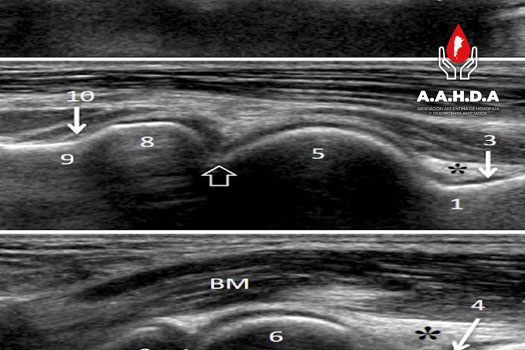

PROTOCOLOS IMÁGEN: ECOGRAFÍA

ECOGRAFÍA EN HEMOFILIA

HEAD-US Ultrasound

HEAD-US Ultrasound escala sinovitis

HEADUS Scoring Sheet

PLANILLA HEADUS